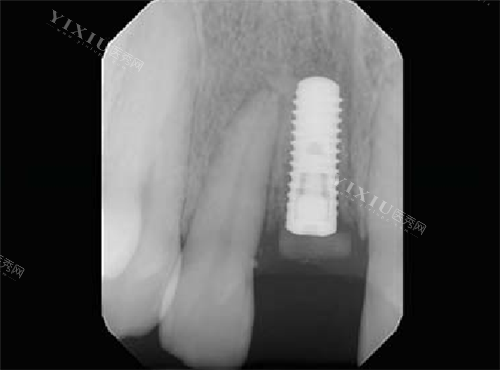

瑞士士卓曼iti种植牙植入后

瑞士士卓曼ITI亲水种植牙

士卓曼种植牙图片